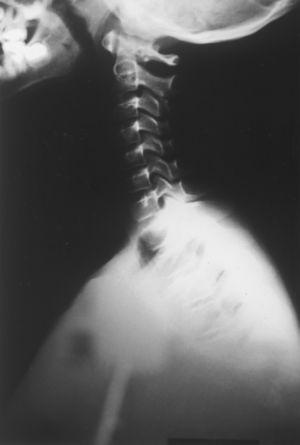

Pruebas complementarias. Radiografía cervical y de tórax (figs. 1 y 2): escápula derecha elevada, apreciándose en columna cervical apéndices costales C6 de predominio derecho.

Figura 1. Radiología de columna cervical: se aprecian apéndices costales de predominio en C6.